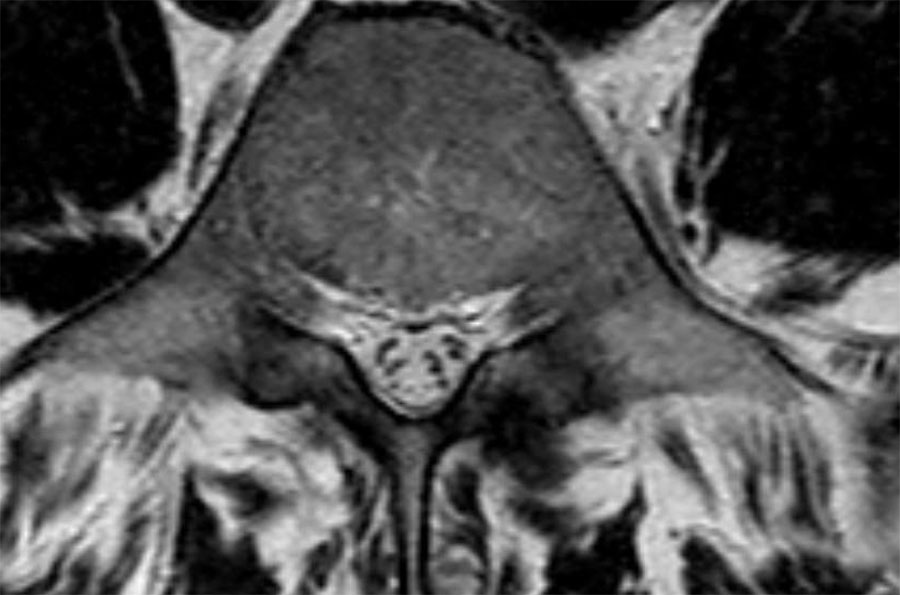

Cuộn qua các hình ảnh để quan sát đường đi của các rễ thần kinh tại mức độ đĩa đệm, ngách bên, lỗ liên hợp và ngoài lỗ liên hợp.

Tại mỗi mức độ có thể thấy các bệnh lý đặc trưng, nhưng có sự chồng lấp đáng kể.

Ví dụ, đĩa đệm có thể thoát vị và gây chèn ép thần kinh tại mức độ đĩa đệm, nhưng cũng có thể di trú xuống tầng thấp hơn và chèn ép rễ thần kinh trong ngách bên, hoặc di chuyển lên trên và gây chèn ép tại mức độ lỗ liên hợp hay ngoài lỗ liên hợp.

Ở bệnh nhân thoái hóa khớp mỏm khớp, các gai xương có thể phát triển vào trong và làm hẹp ngách bên, hoặc phát triển lên trên và làm hẹp lỗ liên hợp.

Khi thoái hóa khớp mỏm khớp nặng xảy ra hai bên, có thể gây hẹp ống sống và chèn ép tất cả các rễ thần kinh tại tầng đó.